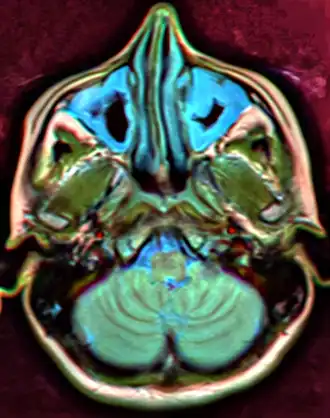

-

CT of chronic sinusitis -

CT scan of chronic sinusitis, showing a filled right maxillary sinus with sclerotic thickened bone -

MRI image showing sinusitis. Edema and mucosal thickening appear in both maxillary sinuses. -